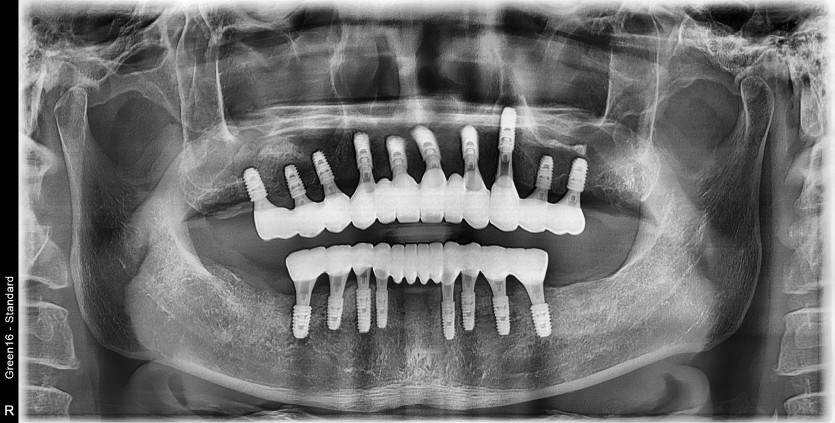

만 52세 전악 상악, 하악 전체 임플란트 증례

전악 전체 임플란트 증례입니다.

18개의 임플란트로 완성하였습니다.